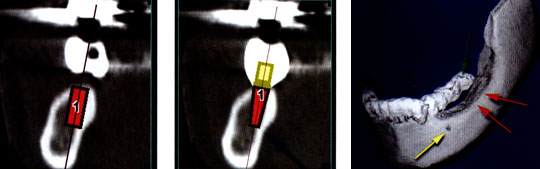

[/userfiles/files/mlt10.jpg]Някои го правят директно със софтуера Планирането на имплантатното лечение, както и практическото му изпълнение е не лека задача и трябва да се прави от подготвени специалисти.

[/userfiles/files/mlt12.jpg]На показаните срезове се вижда съвсем тънка алвеоларна кост, където, след прерязване на острите върхове можеха да се поставят само имплантати MTI, чийто диаметър бе 1.8 мм.

В областта на срез № 18, срезове № 35 и 39, отговарящи съответно на 36,37 и 46-ти зъби, бяха поставени имплантати T.B.R.